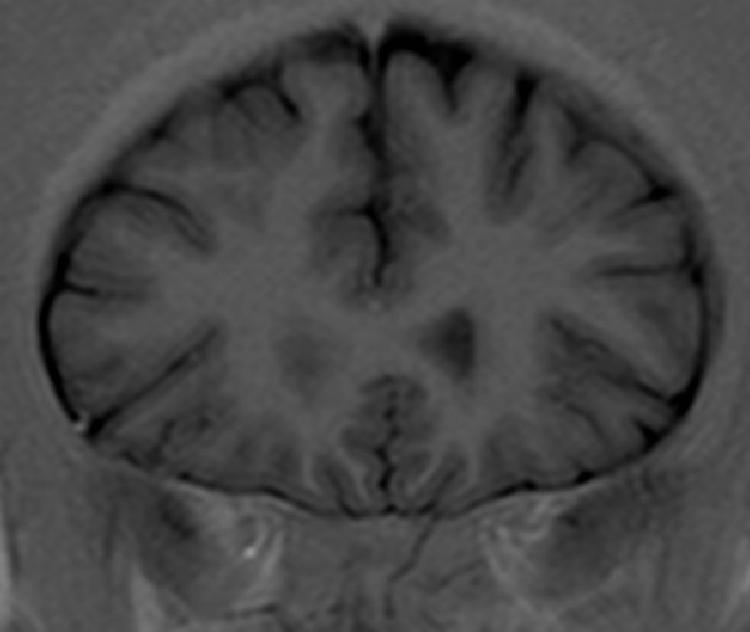

| TRAINING | |

| Testing 1 | Testing 2 |

| Longitudinal cerebral fissure |

| Corpus callosum - genu |

| Anterior cerebral artery and its branches |

| Cingulate gyrus |

| Olfactory tract |

| Temporal lobe |

| Lateral ventricle - frontal horn |